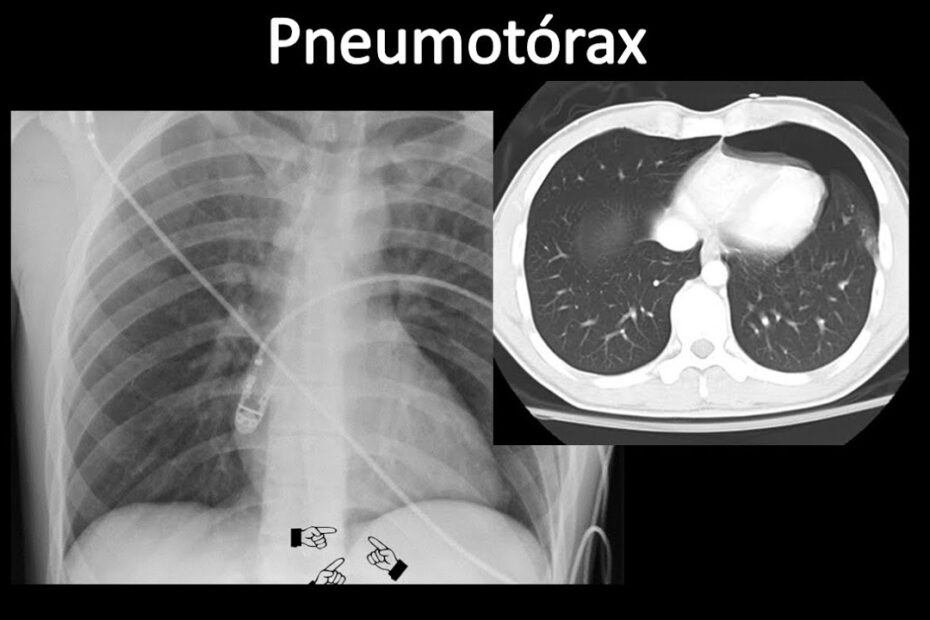

pulmão